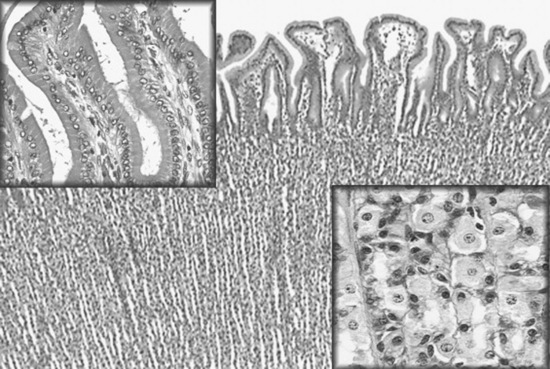

Abdominal radiography is useful to evaluate the small and large intestines for sand accumulation, enterolithiasis, impactions, or small intestinal disorders in foals. When sand is ingested, it generally will accumulate within the large colon along the ventral abdomen8 (Fig. 32-4). Radiography has been found to be a useful method to monitor the resolution of sand impactions after medical management; however, sequential examinations are needed to verify that the volume of sand has reduced.8 If the volume of sand is large enough, it is difficult to determine if an enterolith is present because of summation of the two lesions. Enteroliths are a solid concretion of mineral that usually forms around a nidus, such as a metallic foreign body (Fig. 32-5). The mineral composition is varied, as illustrated by the different opacities present within the enterolith. Radiographs have a 96.4% positive predictive value to detect enteroliths in high-prevalence areas. These enteroliths were generally found to be within the midabdominal radiograph, and 67% of small colon enteroliths caused large colon distention, which was also identified on radiographs.7 Impactions are more difficult to diagnose because usually there is just increased feed accumulation within the abdomen. Although no enterolith or obstruction is identified, granular material can be seen, usually within the ventral colon near the sternal flexure. This is because pelvic flexure impactions will cause the feed material to accumulate orad, causing distention of the left ventral colon (Fig. 32-6). Intestinal disorders such as functional ileus secondary to enteritis (Fig. 32-7) or obstruction secondary to intussusception or meconium impaction (Fig. 32-8) in foals can also be identified on abdominal radiographs. These images show large dilation of the small intestine, and differentiation between functional and mechanical ileus in foals is generally based on the size of the intestine and the volume of gas that is present.9 Evaluation of the abdomen using ultrasound may aid in qualifying the small or large intestinal motility as well as identifying the source of an obstruction if the determination on radiographs cannot be made.